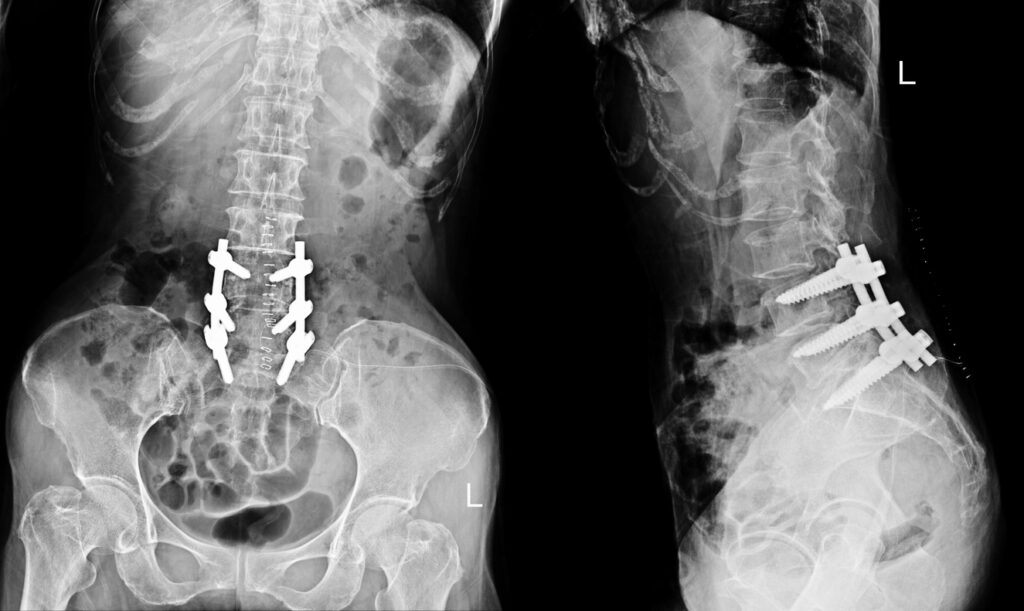

Spinal fusion is a surgical procedure designed to stabilise the spine by permanently joining two or more vertebrae. By eliminating movement between the affected vertebrae, the procedure can reduce pain, improve alignment, and restore stability to the spine. The surgery often involves the use of bone grafts, screws, or metal rods to encourage the vertebrae to heal together as a single, solid bone.

During surgery, the surgeon typically places a bone graft (natural or synthetic) between the vertebrae. Over time, this graft acts as a bridge, encouraging the vertebrae to fuse. Specialised implants such as screws, rods, or plates may also be used to hold the spine in position while the fusion takes place.

- Instrumentation: Metal rods and screws may be used to secure the spine and enhance stability during the healing process.